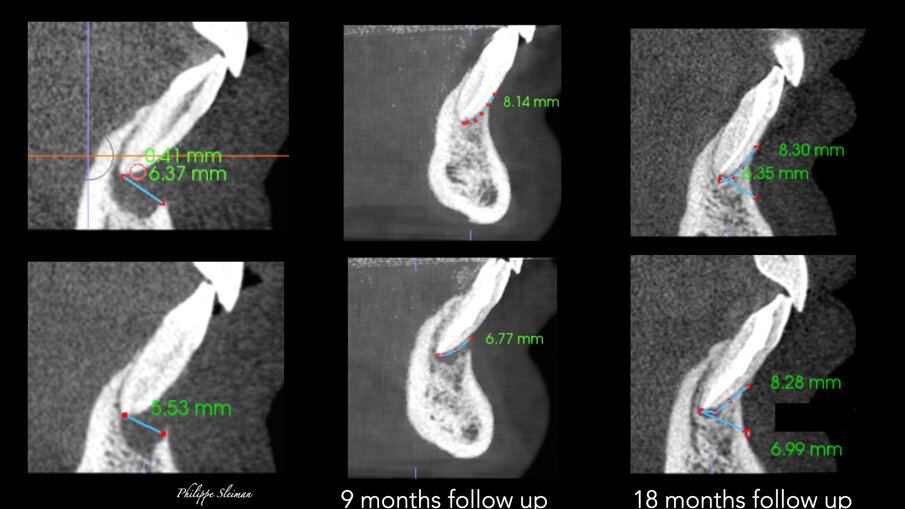

Slike 9a–f: Poređenje vertikalnih prikaza i-CAT skeniranja snimljenih pre operacije (a i b) i tokom devetomesečnog praćenja (c & d) i 18-mesečnog praćenja (e & f) pokazujući kontinuirani rast kosti vertikalno

Nedelju dana posle operacije, šavovi su uklonjeni i postavljen je finalni ispuni u obe pristupne šupljine centralnih sekutića. Urađena je radiografija neposredno nakon operacije, kao i snimak nakon devet meseci od intervencije. Poređenje snimaka pokazalo je apoziciju kosti između dva centralna sekutića (slika 4). I-CAT skeniranje je takođe napravljeno u devetomesečnom period praćenja kako bi se proverio rast kostiju. Horizontalni pogled, uzet na istom nivou kao i preoperativno, jasno je pokazao smanjenje zazora sa 14,11 mm na 4,42 mm. Isti trend u lečenju (slika 5) pokazao je vertikalni pogled -kost na bukalnoj ploči je rasla prema korenu vertikalno (slika 6) skoro 8,2 mm visine tako da je kost bila vraćena i u direktnom je kontaktu sa korenovima zuba. Zaista, kada se obezbedi „skela“ na kojoj može da raste, kost može rasti u svim pravcima, uključujući i vertikalno, gde je postojao otvoreni parodontalni džep.

Poređenje i-CAT skenova napravljenih pre operacije i nakon devetomesečnog i 18-mesečnog praćenja pokazalo je potpuna regeneracija kortikalne i trabekularne kosti sa velikim biološkim detaljima, pokazujući čak i frenum (slike 7 i 8). Preoperativni prikaz kosti jasno je pokazao preoperativni veliki horizontalni i vertikalni defekt kosti i otvoreni parodontalni defekt, a sada se na tom mestu može videti lepo regenerisana kost prirodnog izgleda i nastanak mandibularnog nerva. Na sreću, kost je nastavila da raste vertikalno (slika 9).